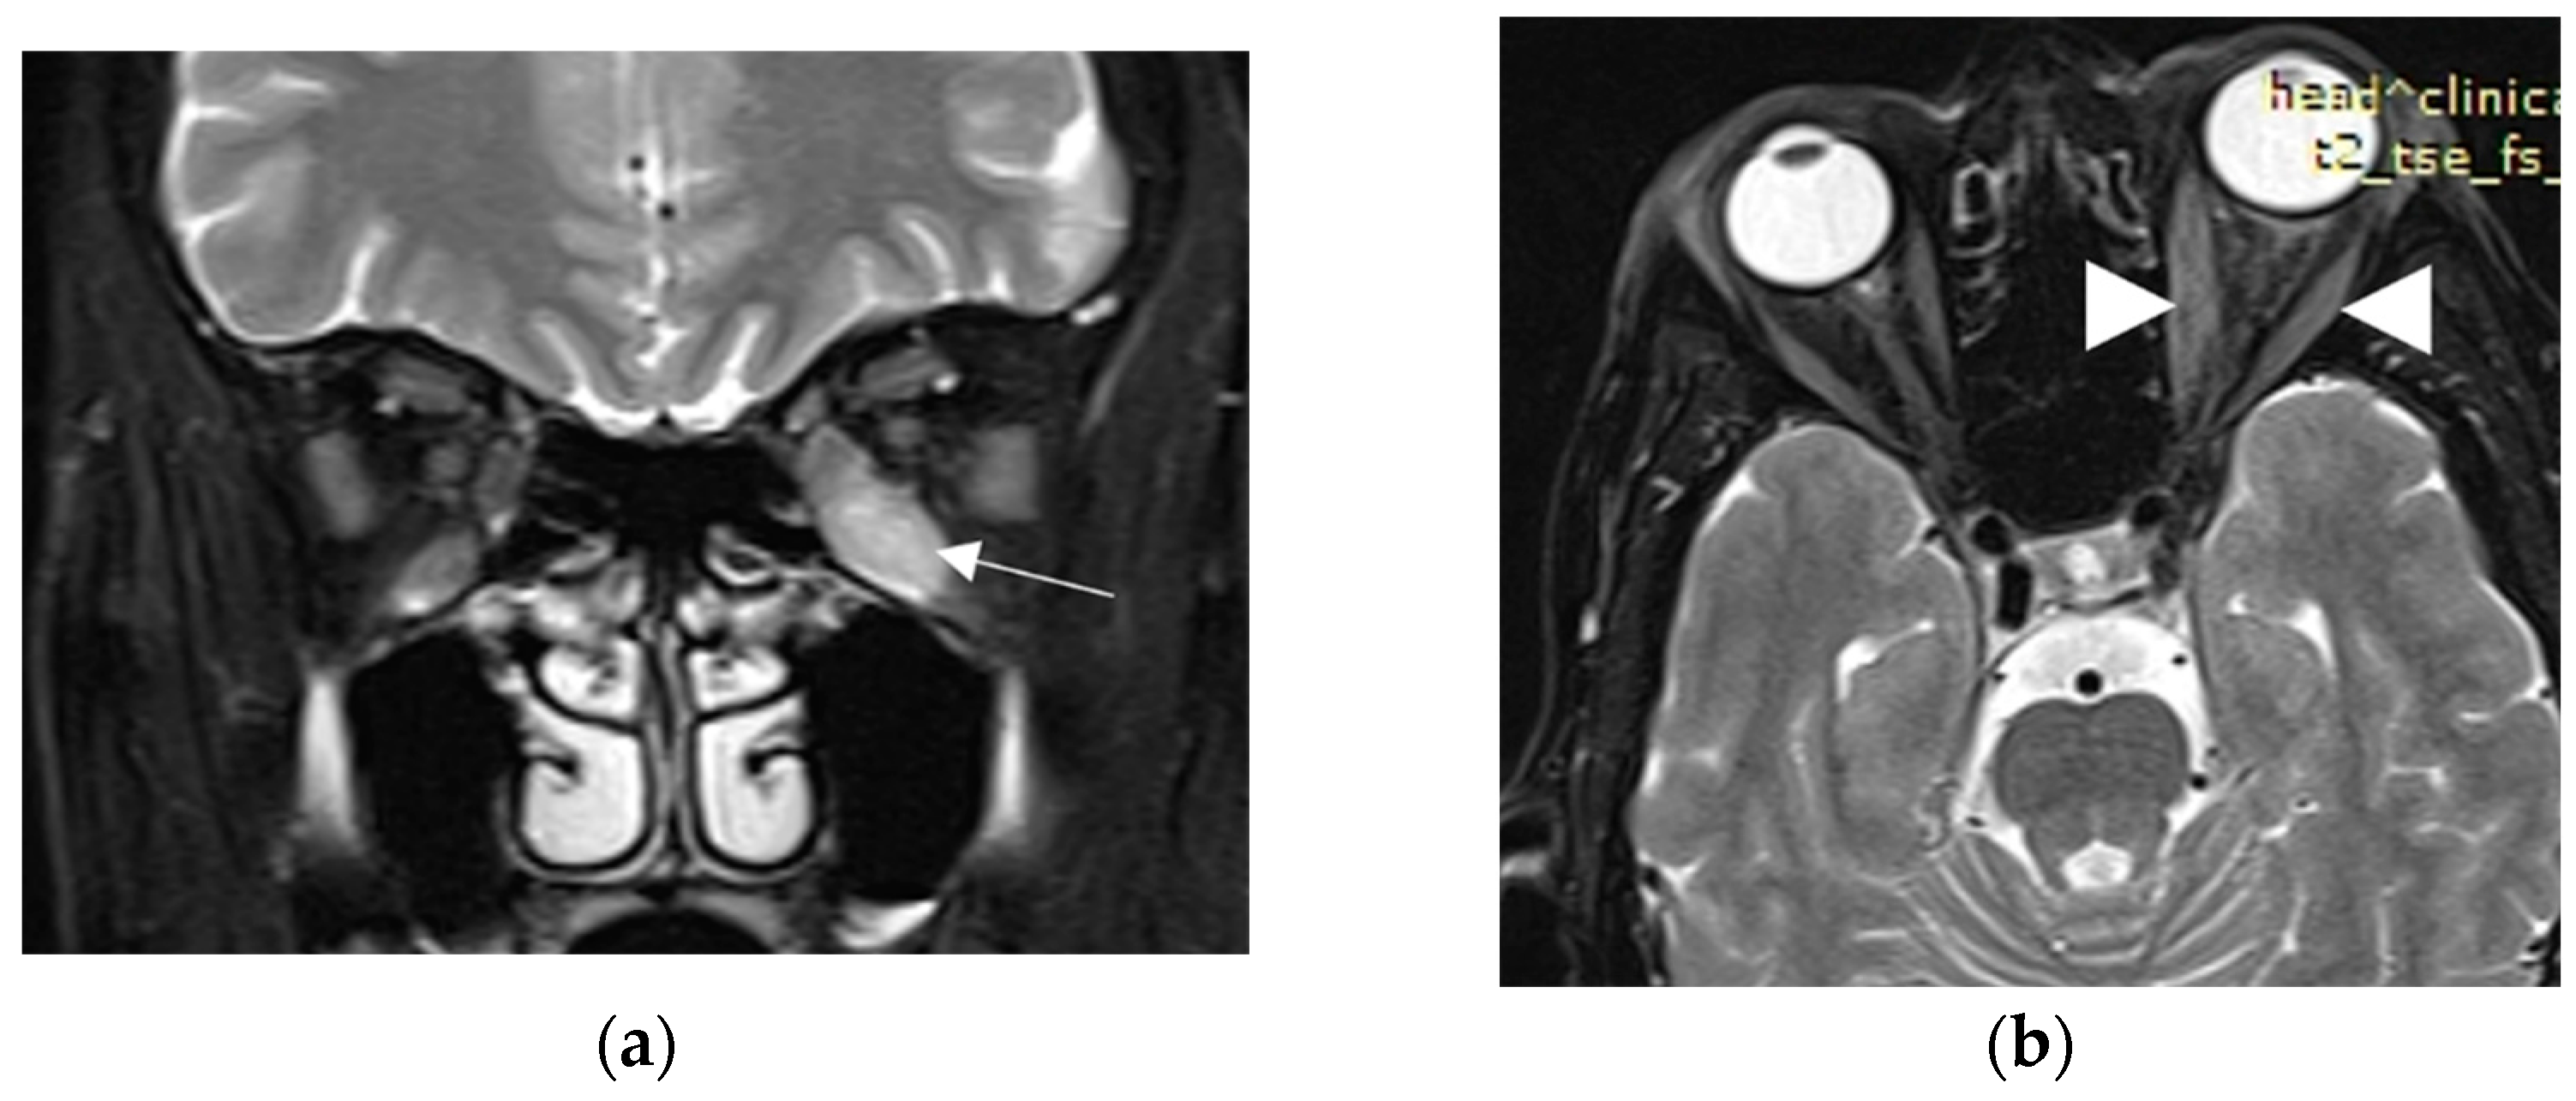

2. Case Presentation